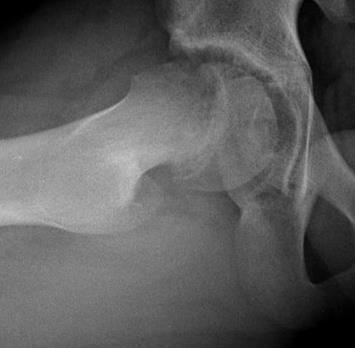

Do charakterystycznych objawów podmiotowych i przedmiotowocyh patologii widocznej na radiogramach należą: 1) ból w pachwinie promieniujący na przednią powierzchnię uda; 2) objaw Kleina-Trethowana; 3) objaw Capenera-Durbina; 4) objaw Drehmanna; 5) objaw Gage. Prawidłowa odpowiedź to: